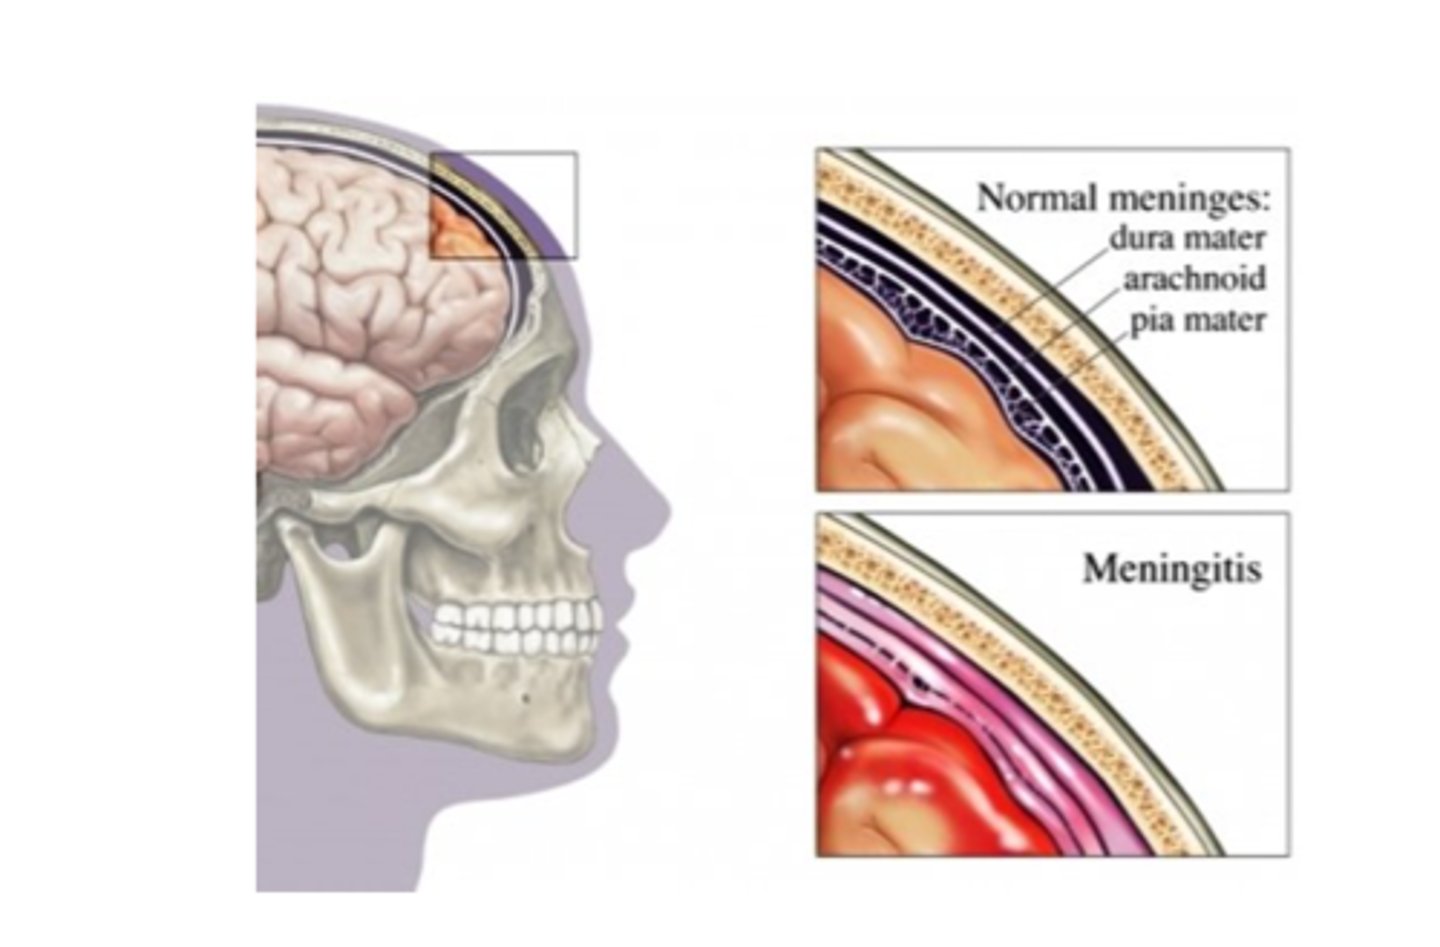

Protection of the CNS

1) scalp and skin

2) skull and vertebral column

3) meninges

Meninges

Connective tissue membranes that lie just external to the CNS organs that:

-Cover and protect the CNS

-Protect blood vessels and enclose venous sinuses

-Contain cerebrospinal fluid

3 Layers (external to internal) of Meninges

Dura Mater,

Arachnoid Mater,

Pia Mater

Dura Mater

First layer of Meninges,

Has layers that can separate to form dural sinuses:

-Periosteum

-Meningeal layer

Arachnoid Mater

Second layer of the Meninges,

Subarachnoid space with cerebrospinal fluid

Pia Mater

Third layer of Meninges

Meningitis

Bacterial meningitis (medical emergency) and viral meningitis,

inflamed meninges